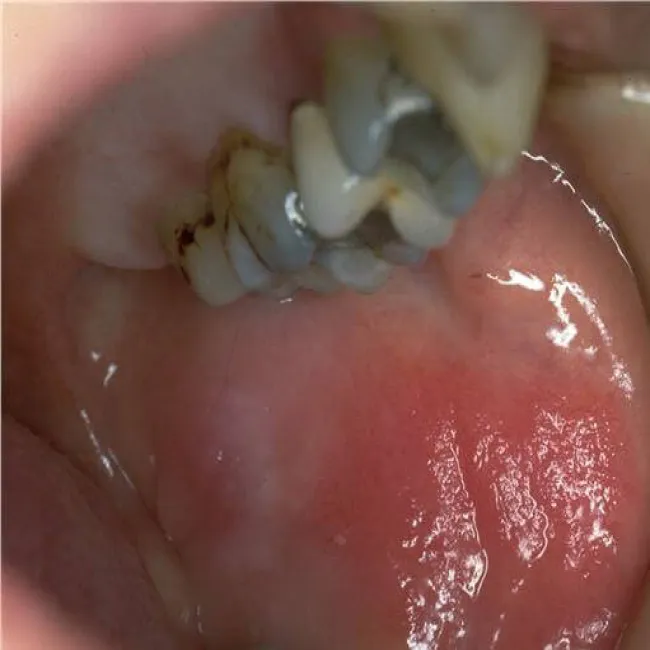

Zespół Brandta, zespół Danbolta-Clossa

Jama ustna